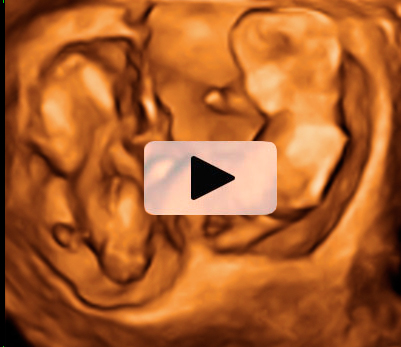

Los movimientos de estos gemelos de 12 semanas de gestación son extraordinariamente claros en la ecografía 4D. Los bebés mueven todo su cuerpo, especialmente brazos y piernas, adoptando multitud de posturas. Destaca el aspecto fieramente humano de los fetos, a pesar de su diminuto tamaño. Cuentan con dos placentas y dos bolsas independientes; la gruesa membrana de separación entre los bebés es visible en el registro ecográfico.

Ecografía 4D de gemelos de 12 semanas moviendo sus extremidades